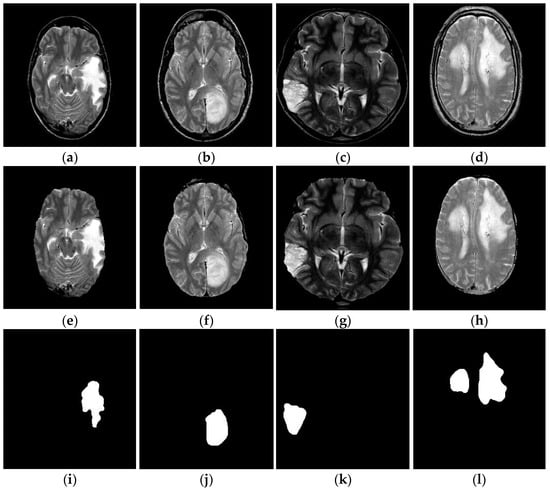

The above process is depicted in Algorithm 2, and the corresponding outputs of FL-MSCM are shown in Figure 7i–l. This figure shows that the proposed segmentation approach significantly separated the tumor and non-tumor regions from skull-free brain MR images.

Figure 7.

Outcomes of the proposed brain tumor segmentation: (a–d) Original brain tumor MR images. (e–h) Skull-stripped images. (i–l) Infected tumor region of the brain MR images by FL-MSCM.